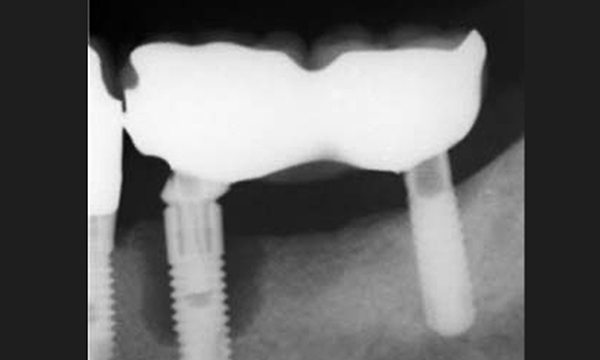

インプラントの歯の部分的なレントゲン写真

インプラントの周囲を清潔に保てないとまず歯茎が炎症を起こし、そこに更に汚れがたまることにより歯周病は進み骨まで溶かしていきます。

一度インプラントが歯周病になると治療は難しいです。

初期であればクリーニングで進行が止まり少し人工の骨を足すことでリカバリーができますが、重度になるとインプラント周囲の骨はなくなりぐらぐらインプラントが動揺します。ここまでくるとインプラントを取らなければなりません。

そこには骨がなく感染した組織があるためインプラントを再度打つことは難しくなります。